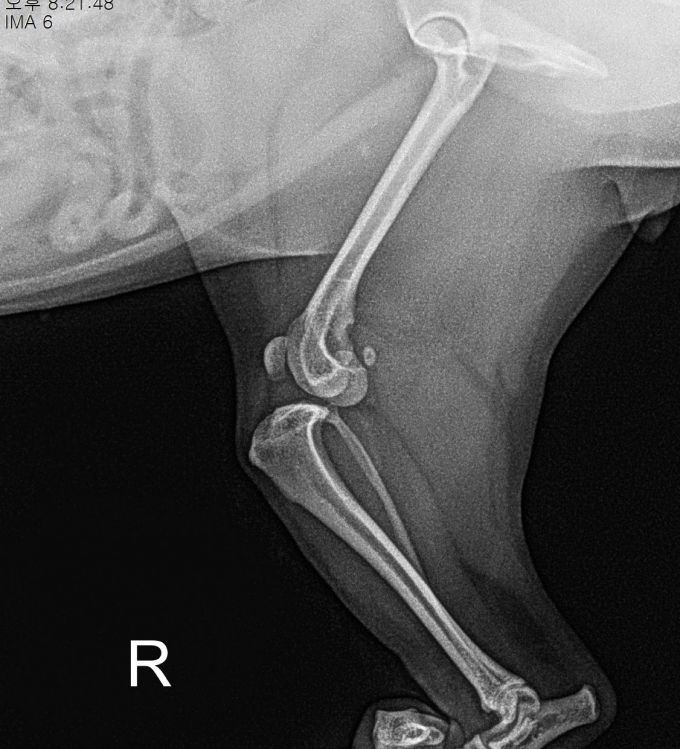

< 손상된 십자인대 >